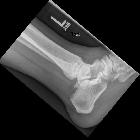

Ankle

impingement. A lateral radiograph demonstrates a large os trigonum

nicht verwechseln mit: Os triangulareThe os trigonum (plural: ossa trigona) is one of the ossicles of the foot and can be mistaken for a fracture.

It sits posterior to the talus on the lateral foot radiograph and represents a failure of fusion of the lateral tubercle of the posterior process. It is estimated to be present in ~7% of adults . Bilateral os trigona are seen in 2% of individuals . The ossicle usually forms between 7-13 years of age and fuses with the talus in a majority of patients by approximately age 17 , otherwise persisting as an os trigonum.